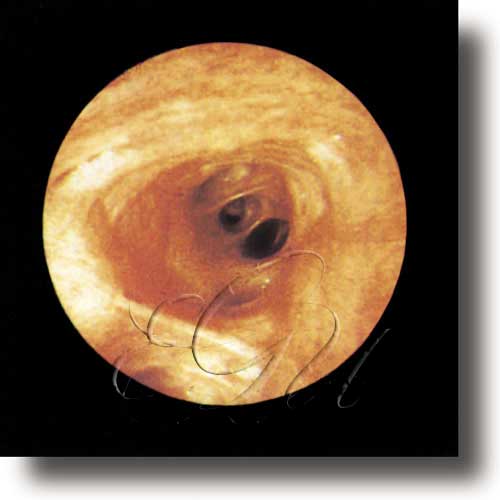

Exame ou inspección feita cun endoscopio da superficie interna das cavidades, dos órganos que conteñen e dos condutos do organismo, como os intestinos ou os órganos reprodutores. Pola maneira de recoller a imaxe, pode ser directa, se a zona que se vai explorar xa forma naturalmente unha cavidade, ou indirecta, se se emprega un gas ou un líquido para formar unha cavidade e poder levar a cabo a exploración. Emprégase con fins diagnósticos e terapéuticos.